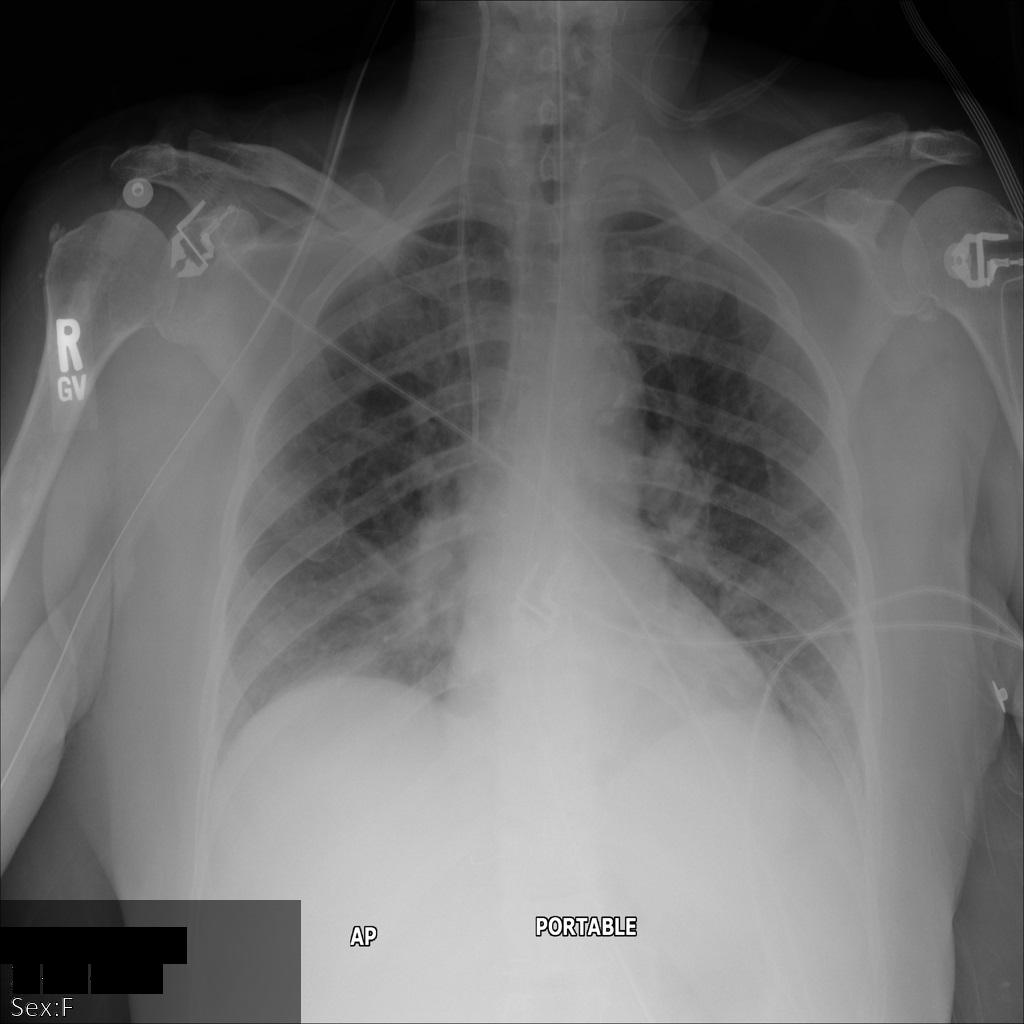

En la siguiente imagen, se muestra una radiografía sin ocultamiento de un paciente:

Después de enviar la imagen a la API de Cloud Healthcare mediante la opción REDACT_SENSITIVE_TEXT, la imagen aparece de la siguiente manera:

Puedes ver que ocurrió lo siguiente:

- Se ocultó el elemento

PERSON_NAMEen la esquina inferior izquierda de la imagen - Se ocultó el elemento

DATEen la esquina inferior izquierda de la imagen

El sexo del paciente no se ocultó porque no se considera texto sensible de acuerdo con los Infotipos de DICOM predeterminados.